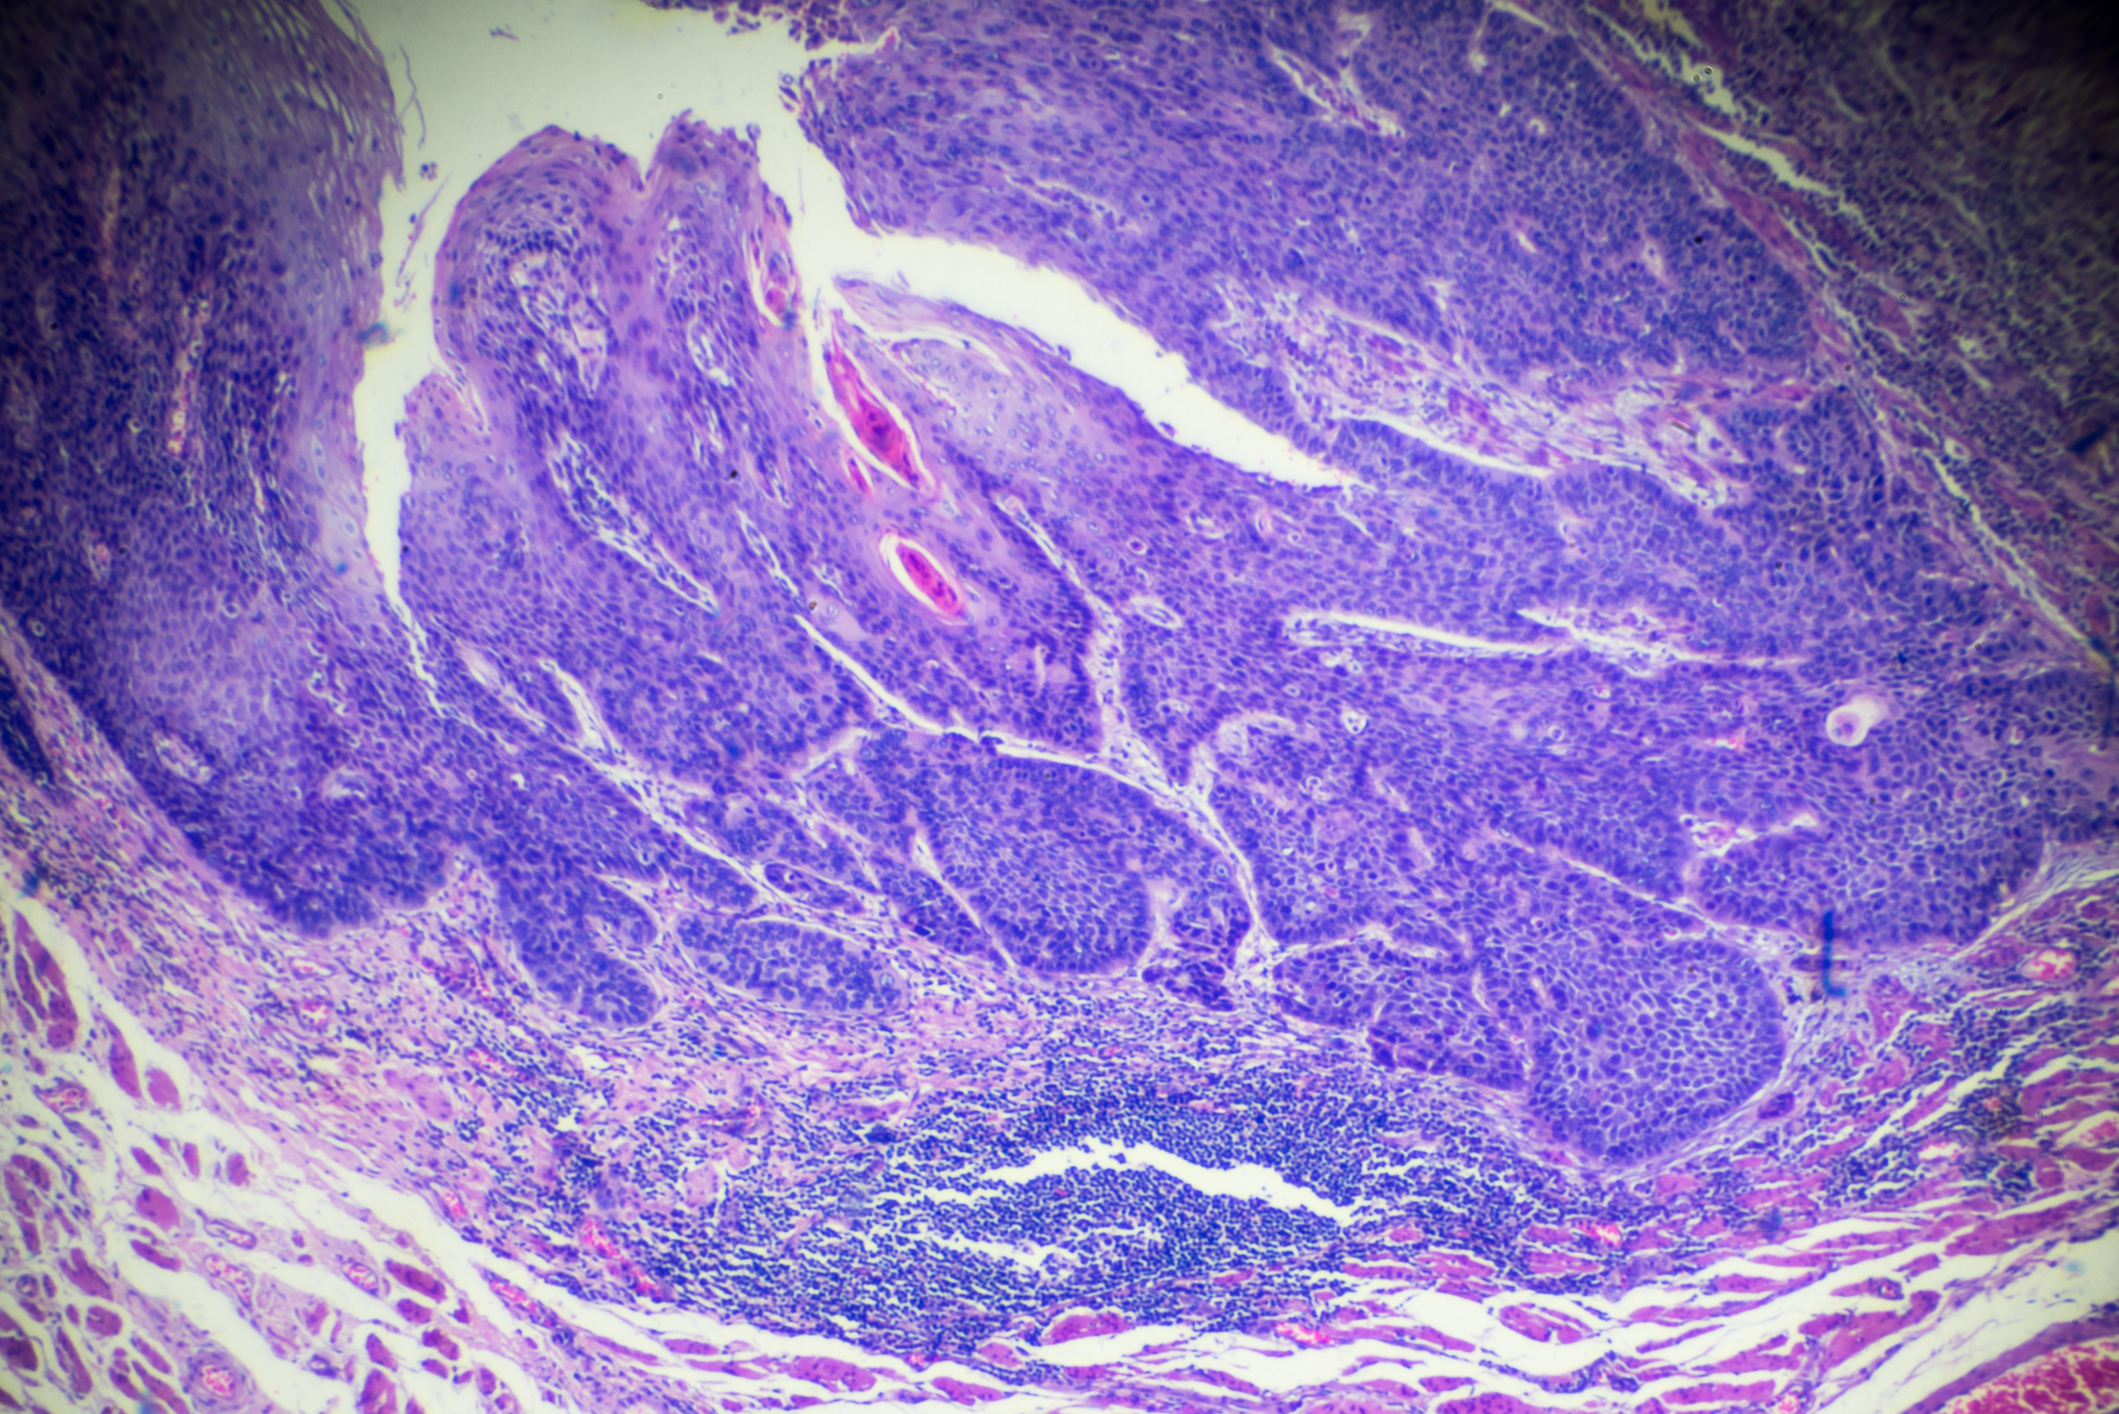

One of the main types of oesophageal cancer is squamous cell carcinoma, which begins in the squamous (skin-like) cells lining the middle and upper part of the oesophagus. Around half of all oesophageal cancers are of this kind.